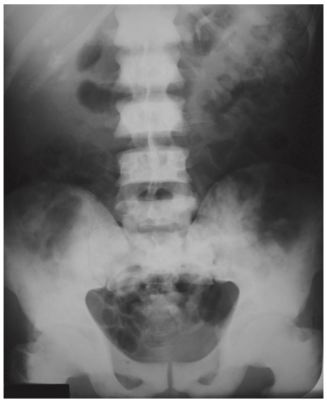

- Trên phim chụp X quang và chụp CT thông thường, toàn bộ hoặc hầu hết các xương đều có màu trắng (xơ cứng).

- Điều này dẫn đến mất hình ảnh lan tỏa của mạng lưới bè xương bình thường trong khoang tủy vì sự thay thế tủy mỡ giữa các tế bào bình thường bằng các yếu tố tạo xương.

- Cũng có thể mất hình ảnh của đường nối vỏ- tuỷ bình thường do mật độ khoang tủy tăng lên bất thường so với vỏ xương (Hình-3).